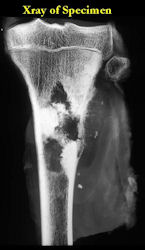

These are examples of the gross pathology specimens of resected conventional osteosarcoma, consisting of both bony and soft tissue areas. X-rays of the specimens are included.

- Osteosarcomas are composed of ossified or non-ossified tissue

- Ossified tissue is yellow-white and hard

- Less ossified tissue is soft and less yellow

- Non-ossified tissue is tan and fleshy

- Most (95%) of conventional osteosarcomas penetrate the cortex and form a large extraosseous soft tissue mass

- The lesion permeates the marrow spaces

- Osteosarcomas usually infiltrate the marrow several centimeters away from the main tumor mass

- Skip lesions may be apparent that are separated from the main tumor by normal marrow

- Osteosarcomas may also have cartilaginous components that appear as translucent lobules, and/or fibrous components that are tan, soft to firm rubbery areas

- Osteoblastic areas are usually white to yellow, firm, hard and gritty

- The consistency of the tumor depends on the amount of osteoid deposition, cartilaginous and fibrous areas

- Foci of hemorrhage and necrosis are common

- Periosteal reactions such as the Codman’s triangle are apparent at periphery of soft tissue mass

- Osteosarcomas rarely penetrate the growth plate grossly

- Invasion of the joint is uncommon but can occur by cortical penetration, joint capsule extension, or extension along cruciate ligaments